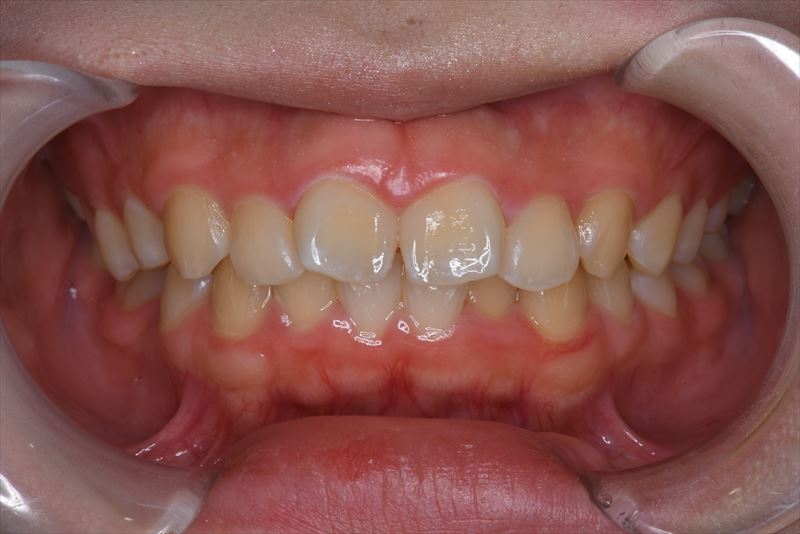

治療前

- 主な症状

- 口元が出ているのが気になる。

- 症状

- 叢生、口唇の突出